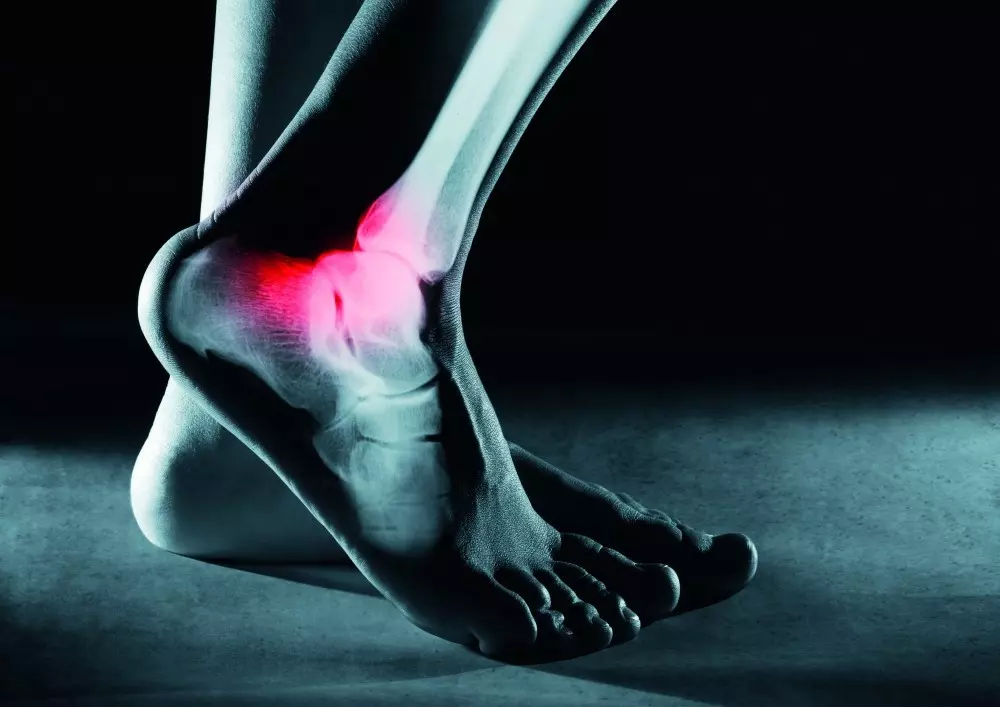

W dziale „Z praktyki gabinetu” prezentujemy, jak krioterapia miejscowa sprawdza się w rehabilitacji stopy. Zespół ekspertów wskazuje, że zimno jest najlepszym środkiem przeciwzapalnym we współczesnej fizykoterapii. W opracowaniu znajduje się opis krioterapii miejscowej, wskazania i przeciwwskazania do terapii oraz możliwość zastosowania jej w sporcie czy po operacjach. Będą mogli zapoznać się Państwo także z opisami kilku przypadków po przebytych urazach stóp.

W tej samej rubryce znajdą Państwo artykuł pt. „Zastosowanie technik masażu głębokiego w leczeniu najczęstszych kontuzji biegaczy. Część 1. Zapalenie rozcięgna podeszwowego”. Mgr Przemysław Czerniak wskazuje, że zapalenie rozcięgna podeszwowego powoduje ból przeciążeniowy podeszwowej strony stopy i okolic pięty, który towarzyszy pacjentom rano oraz podczas biegu. Zwykle wywołane jest ono przez nieodpowiednie obuwie, „zbyt duże obciążenia treningowe w zbyt krótkim czasie oraz zła technika biegu – najczęściej nadmierne pochylanie się lub spięcie stopy w fazie przetaczania”.